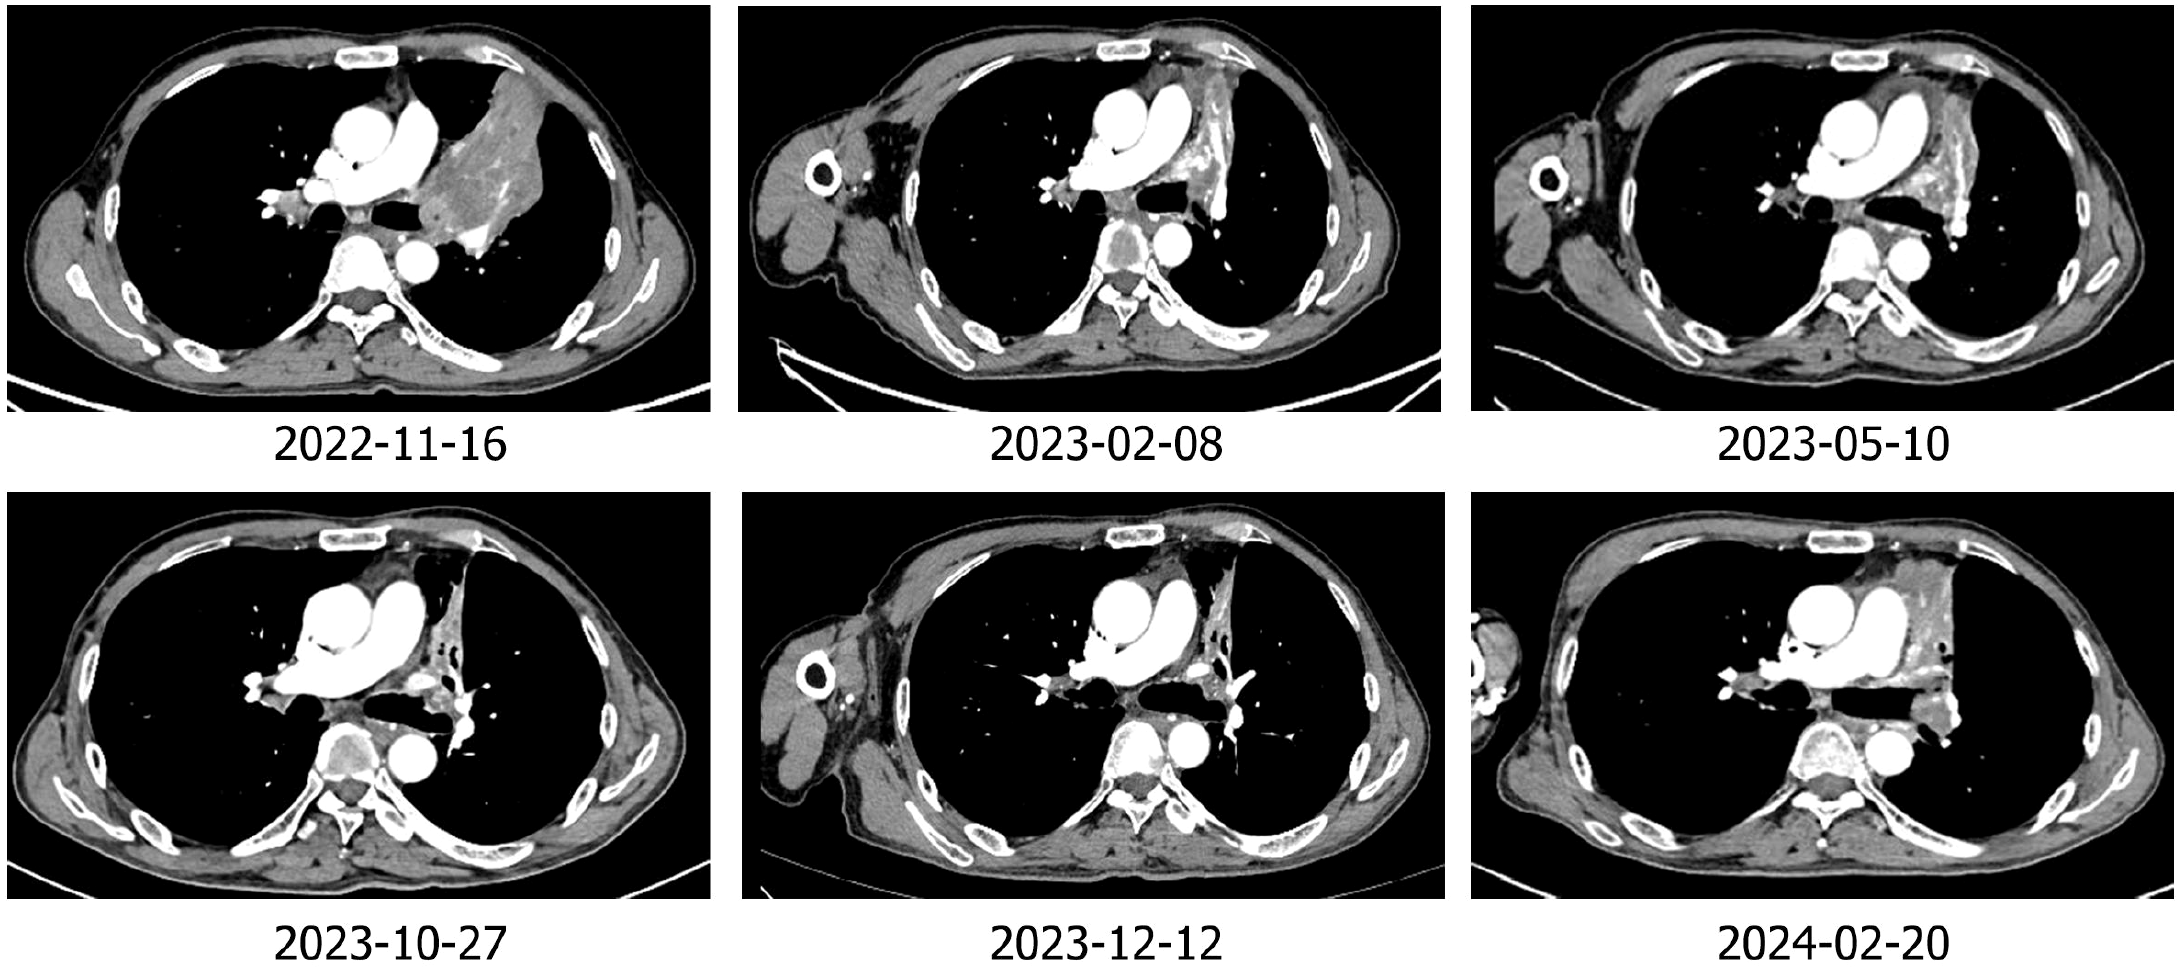

靶免联合治疗期间患者胸部CT显示左肺门病灶持续缩小

• 2022年11月:随后,患者交叉入组到试验组,进行索凡替尼联合特瑞普利单抗治疗,治疗3周期后左肺病灶从9.3 cm缩小至7.9 cm,肿瘤缩小15%,疗效评价为疾病稳定(SD)。

• 持续靶免治疗至2024年2月:2023年8月复查左肺病灶继续缩小31%,疗效评价达到部分缓解(PR);直至2024年2月疾病进展,PFS达15.1个月。